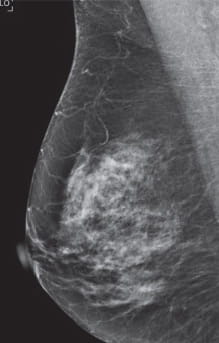

Radiologists classify breast density using a four-level density scale, as determined by a mammogram:

- Category C: Heterogeneously dense

- Category D: Extremely dense

Having dense breast tissue may increase your chance of getting breast cancer. Dense breasts also make it more difficult for doctors to spot cancer on mammograms. Dense tissue appears white on a mammogram; lumps, both benign and cancerous, also appear white. So mammograms can be less accurate in women with dense breast tissue.